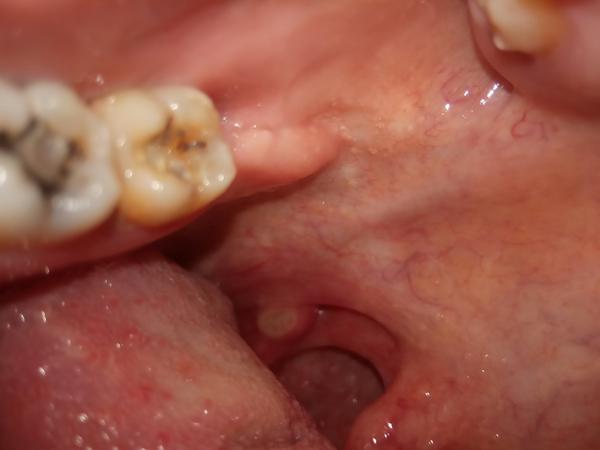

niečo mám na mandli, bolí to ako afta. Hrdlo ma nebolí, teploty nemám. Prvý deň to bola malinká bodka, teraz je tomu tretí deň a vyzerá to takto, zväčšilo sa to.

Občas mávam mandľové kamene, ale toto je niečo iné. Zatiaľ si dávam Jox.

podľa fotografie sa to javí ako afta, môžete pokračovať v aplikácii joxu. ´Dalej môžete ešte kloktať Gargantu alebo Tantum verde a užívať vitamíny skupiny B.